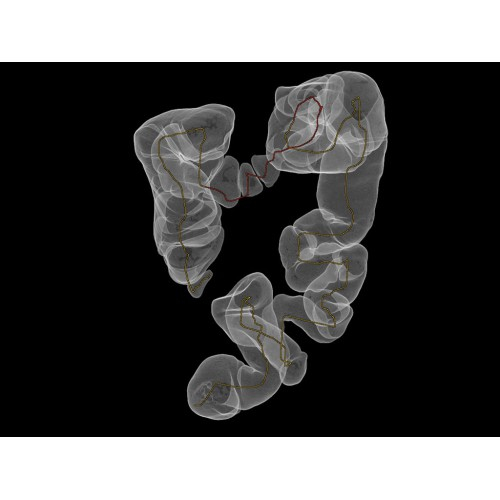

Области применения

Позволяет проводить комплексные исследования всех анатомических зон, включая нейровизуализацию, ангиографию, исследования органов грудной и брюшной полости. Особенно эффективен для раннего выявления онкологических заболеваний.

Специализированные исследования